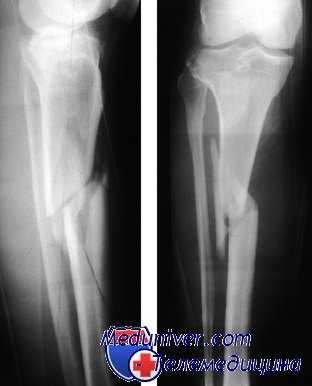

(Слева) Рентгенография в передне-задней проекции: определяется спиральный перелом проксимального диафиза большеберцовой кости.

(Справа) На боковой проекции у этого же пациента определяется косой спиральный перелом малоберцовой кости. Перелом проксимального диафиза малоберцовой кости, в частности, при спиральной ориентации должно подтвердить необходимость поиска сопутствующей травмы лодыжки, к примеру, комплекса Мезоннева. Полное перекрытие большеберцовой кости головкой малоберцовой кости не указывает на вывих ПБМС, но на плохое укладывание пациента вследствие боли. Обратите внимание на отступ мыщелков бедренной кости. (Слева) На рентгенографии лодыжек в косой проекции у этого же пациента определяется расширение медиального голеностопного сустава с небольшим отрывным осколком В рядом с медиальным лодыжечным краем, что подтверждает наличие травмы Мезоннева.